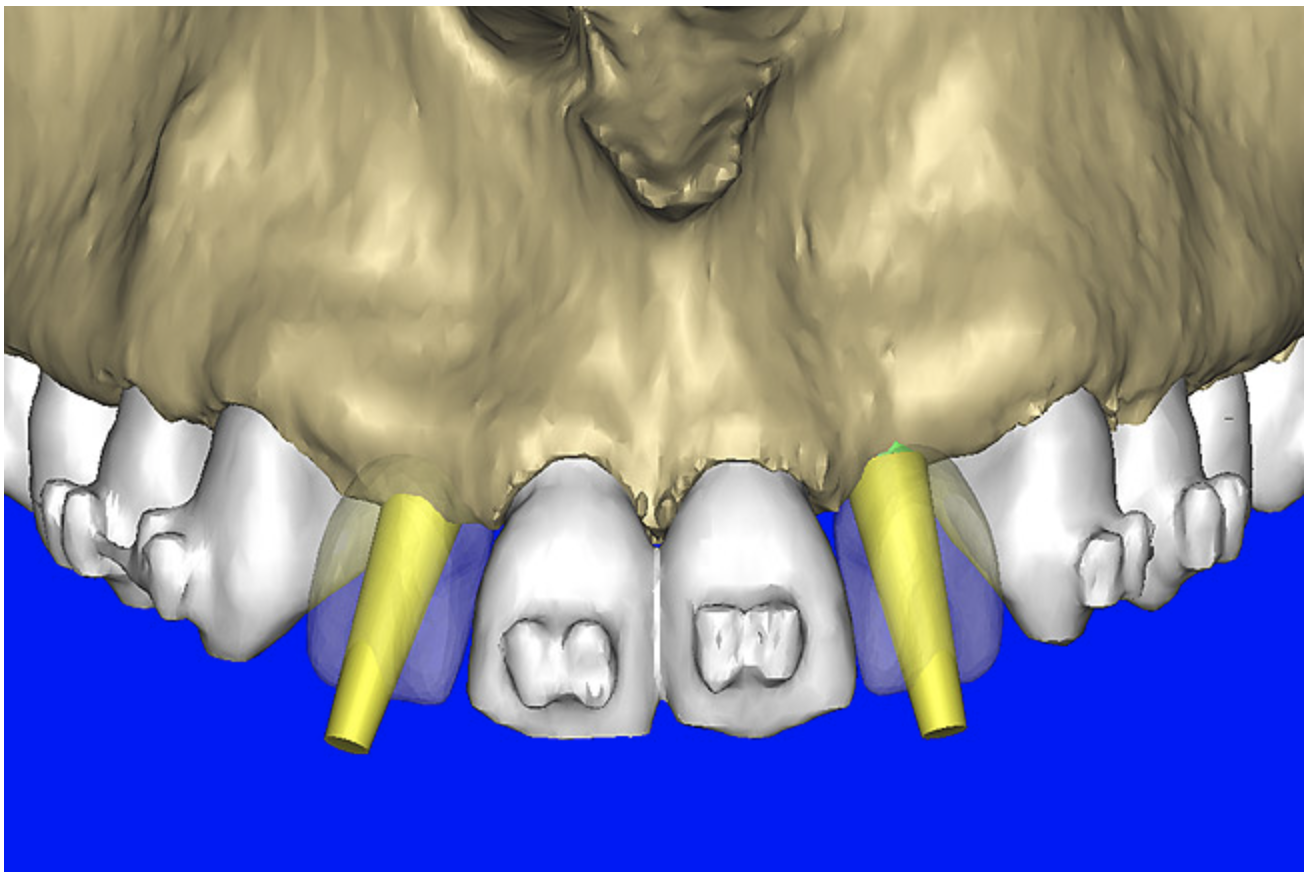

After the basic plan had been established, it was re-evaluated using interactive 3D images. The reconstructed 3D view of the maxilla clearly illustrated the extent of the bilateral facial concavities, and the root eminences of the adjacent and posterior teeth (Figure 7A). The placement of the virtual implants then was evaluated to ensure that the facial cortical plate was not perforated (Figure 7B). The implants were labeled individually as “7” and “10,” with the simulated yellow abutment projection indicating the facial-lingual inclination through the bone to the level above the incisal edge of adjacent teeth. The ability to gain a better understanding of these individual root forms can not be underestimated. The dental literature has suggested certain parameters for placing implants near teeth and implants next to other implants. However, there is little scientific 3D documentation to support these suggested rules.5-10 The use of an interactive treatment-planning software application permits closer scrutiny of previously difficult-to-visualize areas, and can now be used to redefine perceptions of spatial positioning of implants, especially when in close proximity to natural tooth roots, vital anatomy, and adjacent implants.27-29

Figure 7a  The 3D reconstruction showed (A) the facial concavities and root eminences, and allowed (B) for evaluation of virtual implant placement to ensure the facial cortical plate was not perforated.

Figure 7b  The 3D reconstruction showed (A) the facial concavities and root eminences, and allowed (B) for evaluation of virtual implant placement to ensure the facial cortical plate was not perforated.